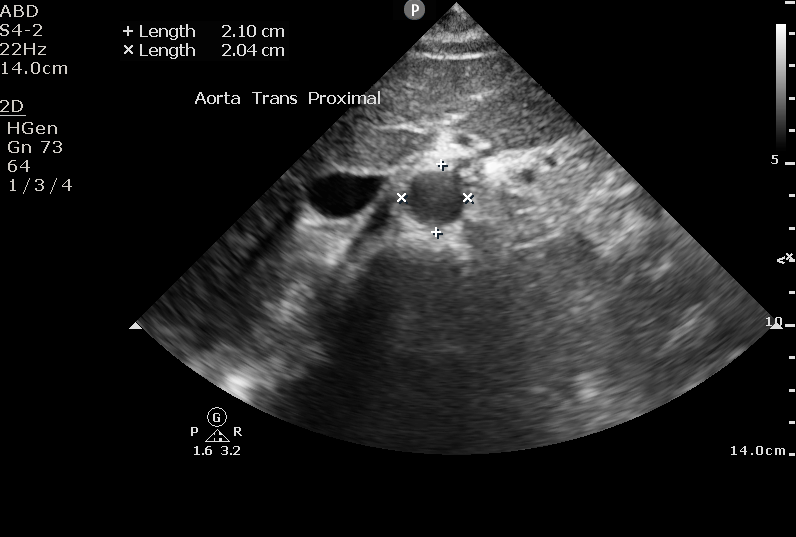

Identify the aorta based on anatomy, not on pulsatility or color flow (there are times where the IVC can appear to be pulsatile and may lead to misidentification). The aorta should appear as a “sad cookie monster” with the IVC and aorta making up the eyes, and the vertebral body making up the frown. You can identify the vertebral body as a hyperechoic “frown” with anechoic shadow behind it.

Measure the aorta anterior the posterior, outside wall to outside wall. We want to overestimate the size in order to be as sensitive as possible. Fusiform aneurysms that would only show up with lateral wall to lateral wall measurements are very rare. Also, the lateral walls on ultrasound will be less accurate due to the direction of the beam and artifact than the anterior and posterior walls. Normal aortic measurement should be less than 3cm, with the risk of rupture greatly increasing over 5.5cm.